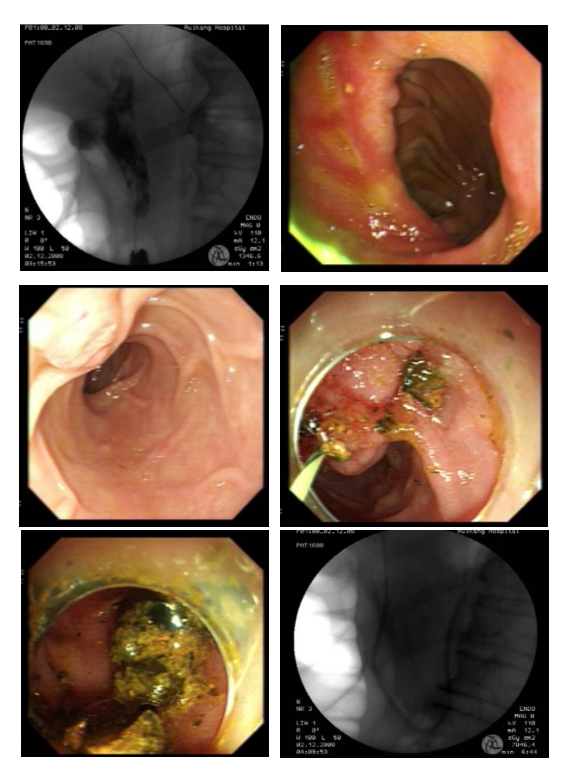

郑东林主任带领的ERCP团队,术前结合了患者因“消化道穿孔”行胃大部分切除(毕II式胃大切)术后患者十二指肠乳头及其开口异于一般普通人等情况,制定了完善的ERCP手术方案。术中,团队熟练配合,坚持不懈,调整常规操作方法,克服了因胃大部分切除(毕II式胃大切)术带来的各种操作困难、顺利进行逆行胆管造影,成功取出了胆总管内的多颗结石,解除了胆道梗阻后,引流出较多的脓性胆汁,术后患者安返病房。

图二:ERCP取石术